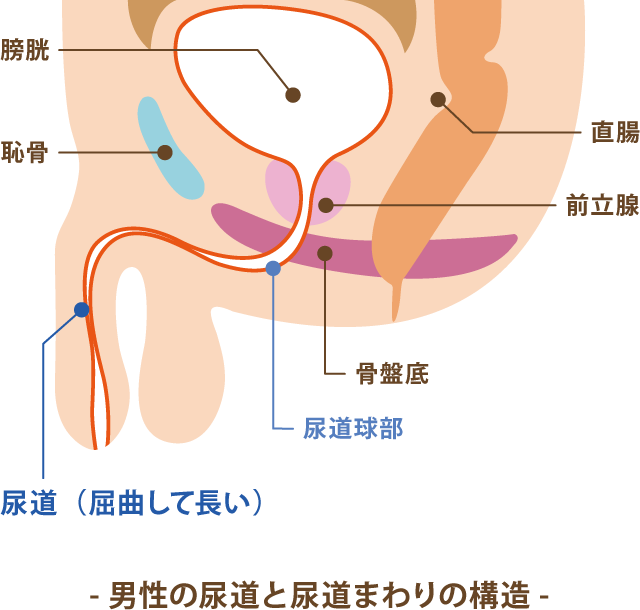

前立腺炎の場合、一般的には会陰部(肛門の前)の鈍痛、 睾丸の鈍痛、排尿痛があげられます。 そして、前立腺炎では多くの場合、この会陰部に痛みが生じます。 会陰部の痛み 急性前立腺炎の場合 急性前立腺炎の場合は、高熱と会陰部痛をともなうため、 男性 会陰部にしこり person 30代/男性 前も相談させて頂きました。 だんなが睾丸のすぐ下から肛門の間にしこりを発見しました。 去年には肛門周囲膿瘍で入院したこともあり、診察を受けに行きましたが、経過は大丈夫で、しこりについては1919 男性 男性の尿道は長く、外尿道口から入った細菌は、膀胱に達する前に排尿によって流されることが多い。前立腺からの分泌液には、細菌の侵入を防ぐ働きがある。 女性 女性は、男性に比べて、尿道が短い上、肛門や膣前庭部と外尿道口が近いので、その分、細菌が膀胱の中に入りやすい。

尿路感染症 藤田医科大学 医学部 腎泌尿器外科学講座